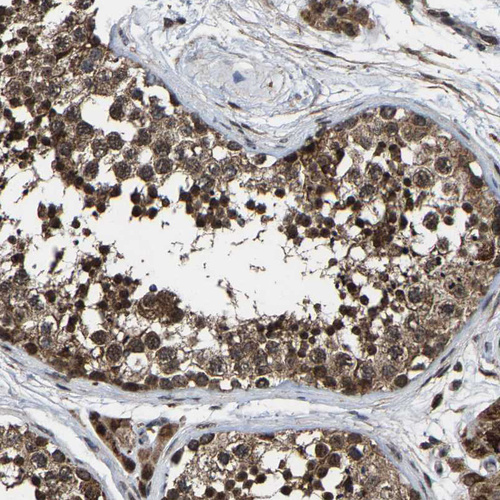

Immunohistochemical staining of human testis shows strong granular cytoplasmic positivity in cells in seminiferous ducts.